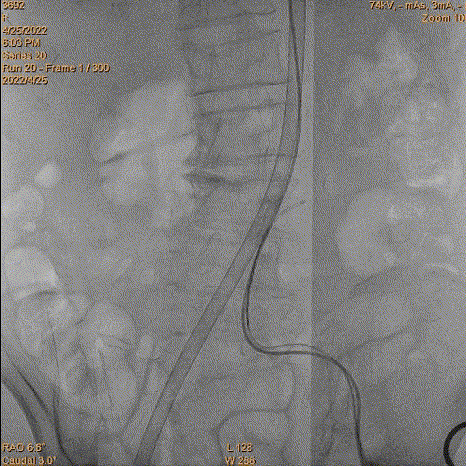

4、跨瓣:瓣膜跨瓣出现困难,计划使用圈套器。由于没有22F大鞘,内连鞘无法拆卸,选择左侧穿刺导入导管。右侧双导丝,送入Lunderquist,心室较大。扩张后,血压较稳定。经尝试无法退球囊,撤出系统。通过对侧使用抓捕器,将导丝全撤,导入AL1.0导管重新跨瓣。鉴于左侧入路有角度,使用泥鳅导丝带上导管,做圈套器。顺利抓住J型导丝,抓捕器顺利抓捕瓣膜过瓣。

重新过瓣

瓣膜过瓣